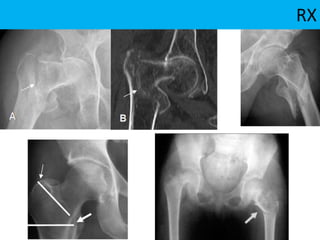

RX

Radiología